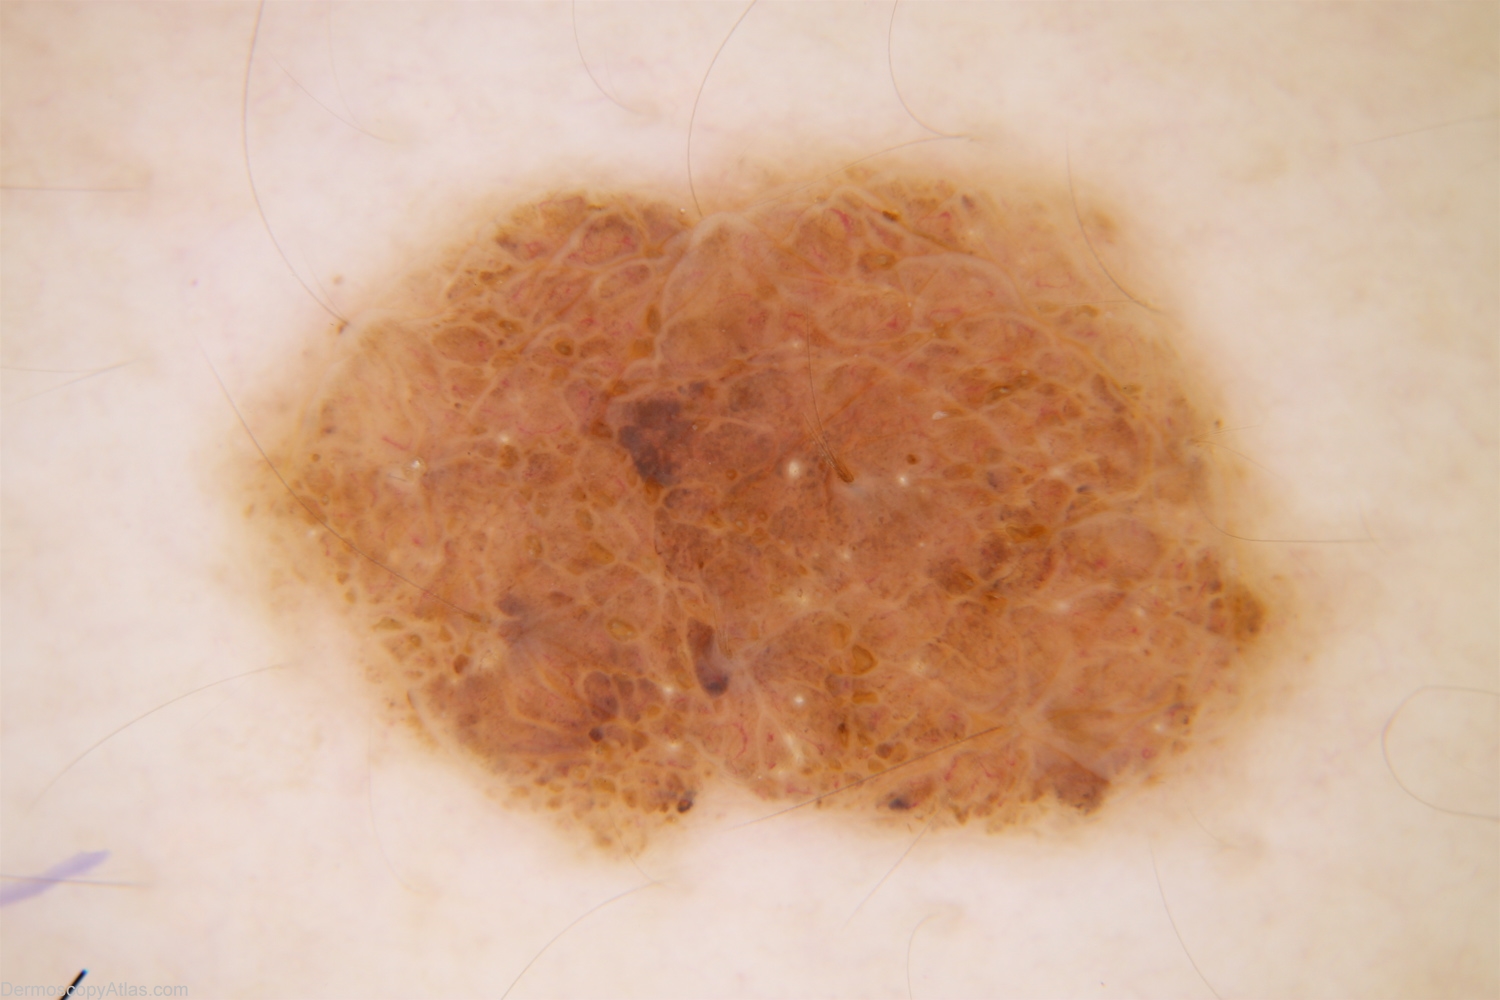

Diagnosis - Congenital nevus

Diagnosis: Congenital nevus